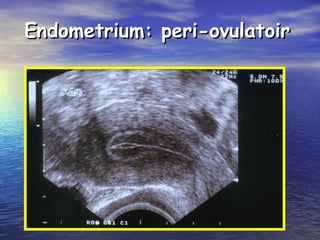

Endometrium: peri-ovulatoirEndometrium: peri-ovulatoir